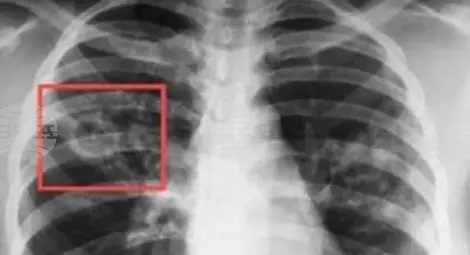

Започват безплатни прегледи за туберкулоза в цялата страна

В България диагностиката, лечението и профилактиката на туберкулозата са безплатни, независимо от здравноосигурителния статус на гражданите. Министерството на здравеопазването осигурява всяка година както финансов ресурс за противотуберкулозни лекарства от първи ред, лекарства за химиопрофилактика, ваксини, диагностикуми и консумативи за лабораториите, така и финансиране на болниците за лечение на туберкулоза. Болестта е лечима и предотвратима, стига да бъде открита навреме и да бъде проведено качествено лечение.